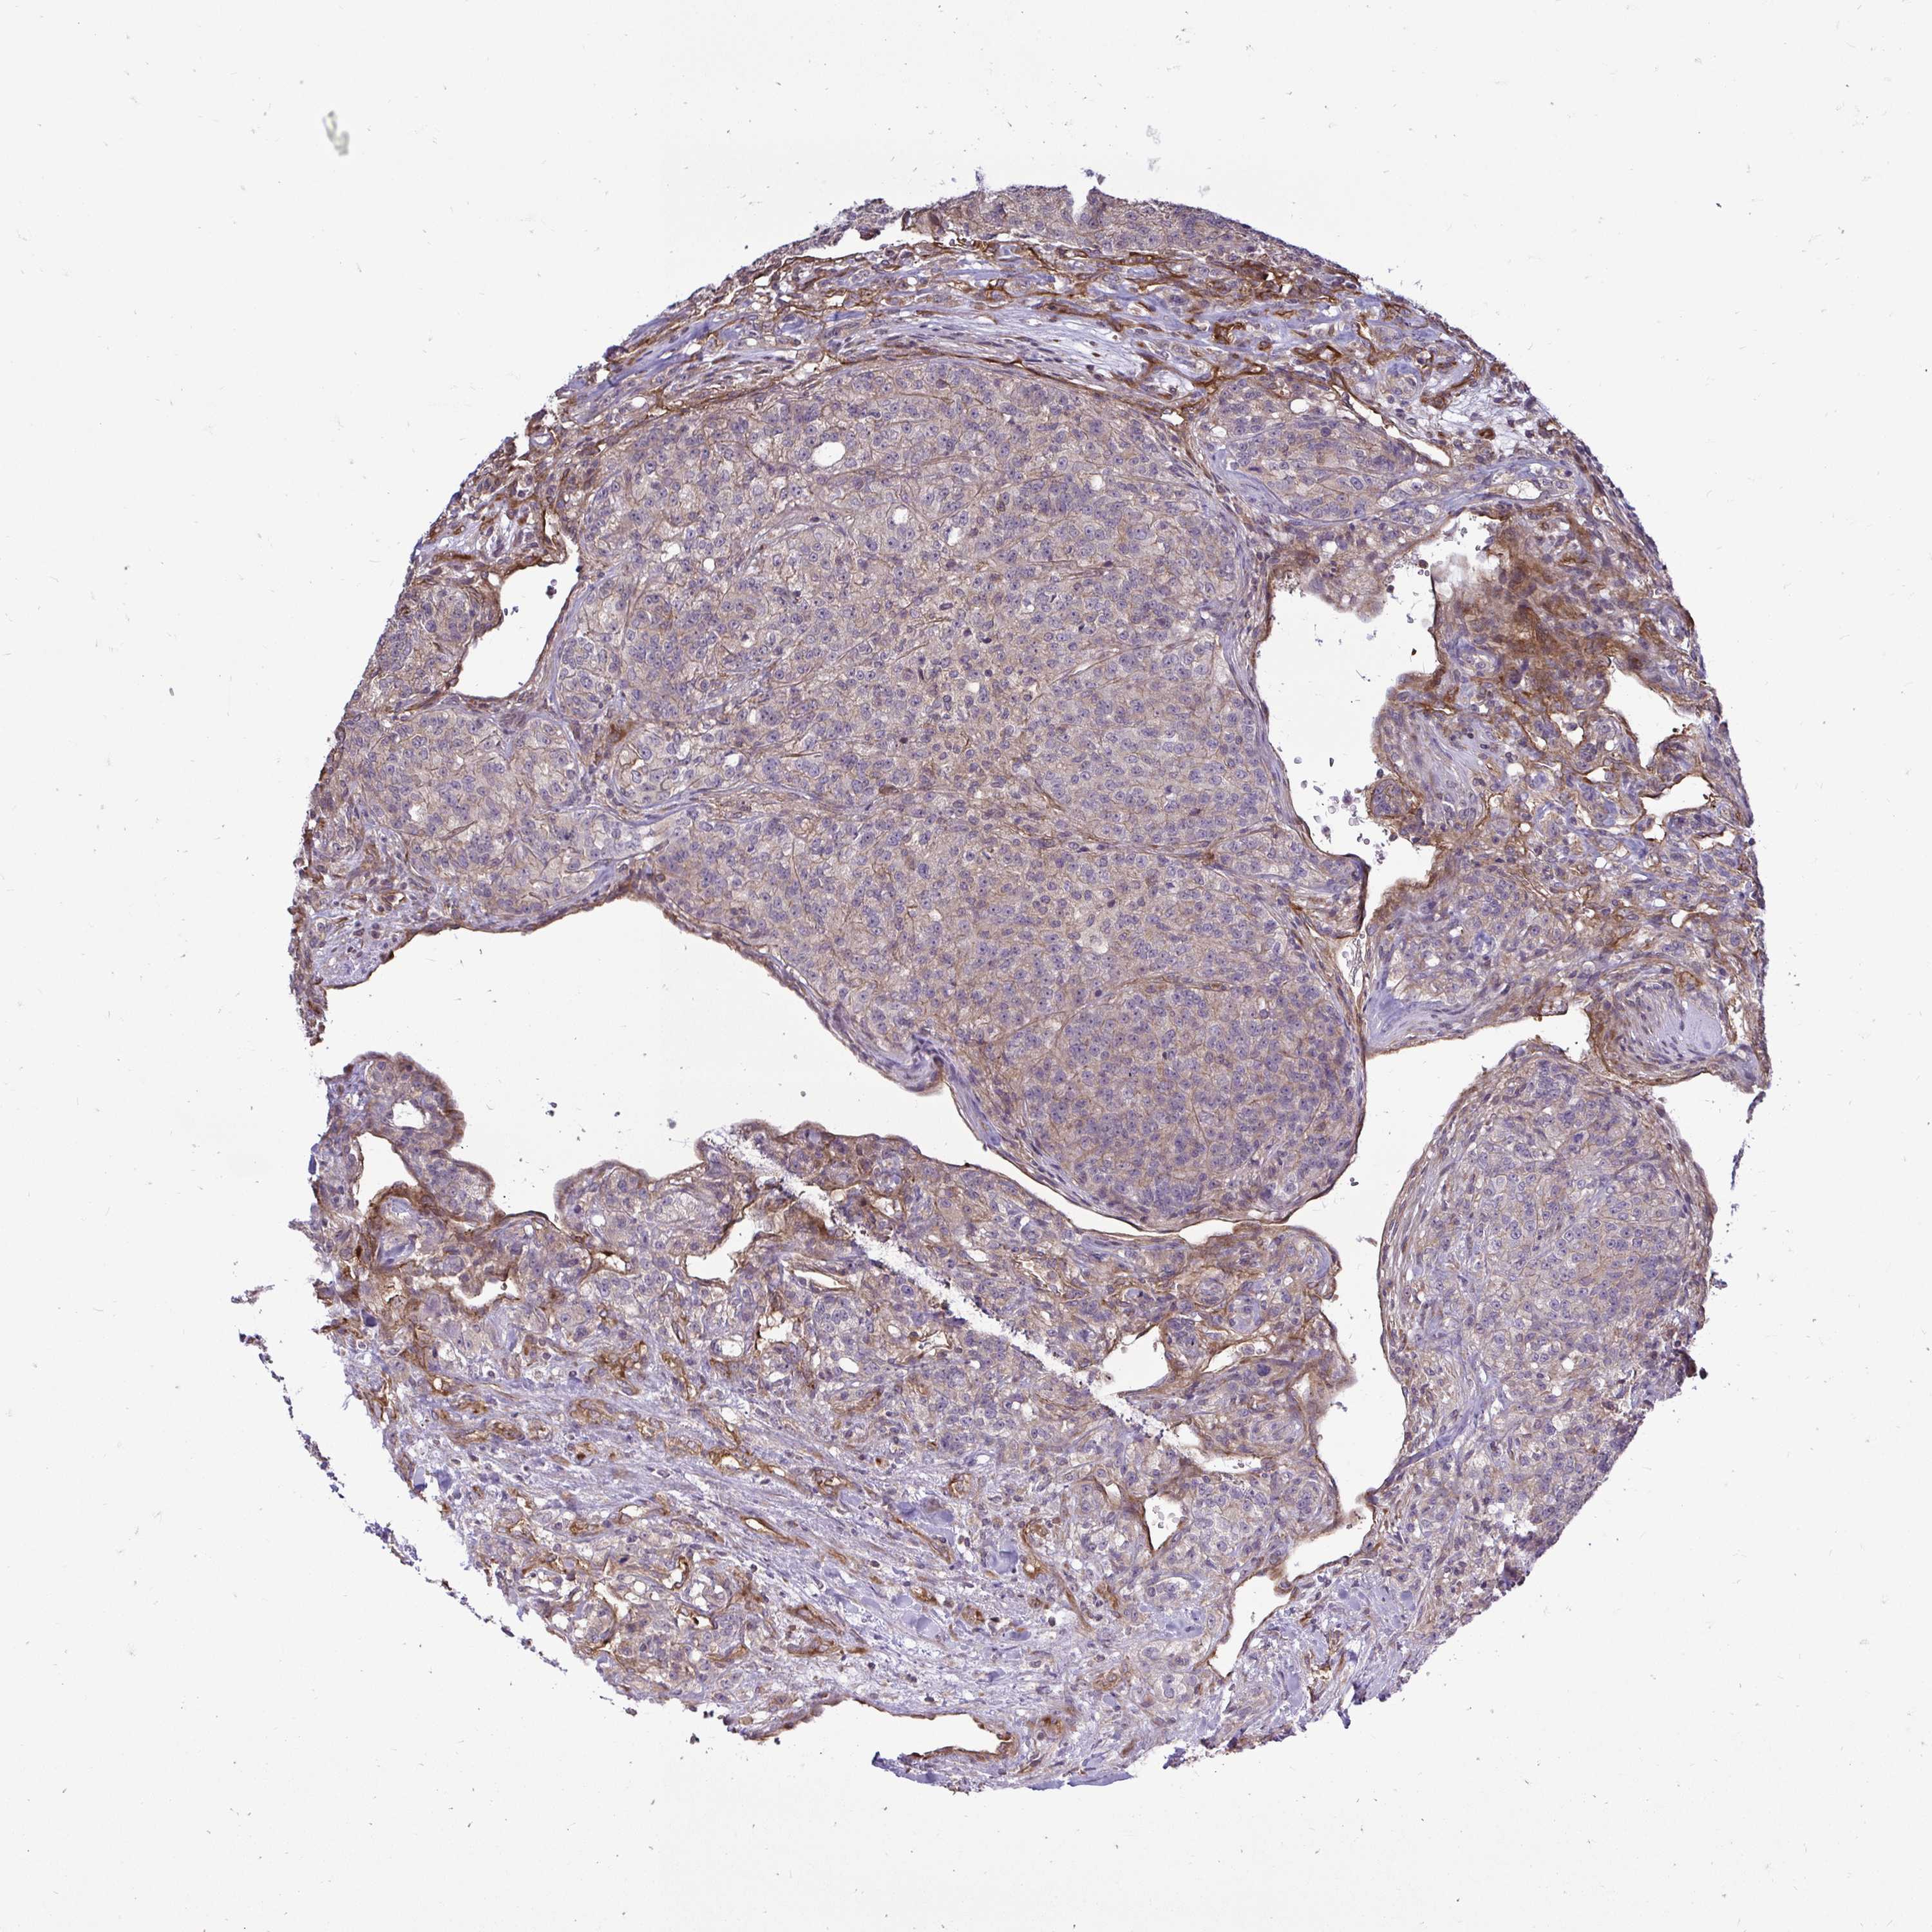

KIDNEY RENAL CLEAR CELL CARCINOMA (VALIDATION) - Interactive survival scatter ploti

The Survival Scatter plot shows the clinical status (i.e. dead or alive) for all individuals in the patient cohort, based on the same data that underlies the corresponding Kaplan-Meier plots. Patients that are alive at last time for follow-up are shown in blue and patients who have died during the study are shown in red.

The x-axis shows the expression levels (FPKM) of the investigated gene in the tumor tissue at the time of diagnosis. The y-axis shows the follow-up time after diagnosis (years). Both axes are complimented with kernel density curves demonstrating the data density over the axes. The top density plot shows the expression levels (FPKM) distribution among dead (red) and alive patients (blue). The right density plot shows the data density of the survived years of dead patients with high and low expression levels respectively, stratified using the cutoff indicated by the vertical dashed line through the Survival Scatter plot. This cutoff is automatically defined based on the FPKM cutoff that minimizes the p-score. The cutoff can be changed by dragging the vertical line or by entering a cutoff value in the square labeled "Current cut-off".

Under the Survival Scatter plot the p-score landscape (black curve; left axis) is shown together with dead median separation (red curve; right axis). Dead median separation is the difference in median mRNA expression between patients who have died with high and low expression, respectively. It is calculated as follows: median FPKM expression of dead patients with high expression - median FPKM expression of dead patients with low expression. This is intended to aid the user in visually exploring custom cutoffs and the associated p-scores and dead median separation.

Individual patient data is displayed and can be filtered by clicking on one or more of the category buttons on the top of the page. Categories describing expression level and patient information include: high, low, alive, dead, female, male and tumor stages. The scale of the x-axis can be toggled between linear and log-scale by clicking on the "x log" button. Mouse-over function shows TCGA ID, patient information and mRNA expression (FPKM) for each patient.

& Survival analysisi

Kaplan-Meier plots summarize results from analysis of correlation between mRNA expression level and patient survival. Patients were divided based on level of expression into one of the two groups "low" (under cut off) or "high" (over cut off). X-axis shows time for survival (years) and y-axis shows the probability of survival, where 1.0 corresponds to 100 percent.

FUT10 is not prognostic in Kidney Renal Clear Cell Carcinoma (validation)

: 3.32

Average pTPM 2.9

Number of samples 100